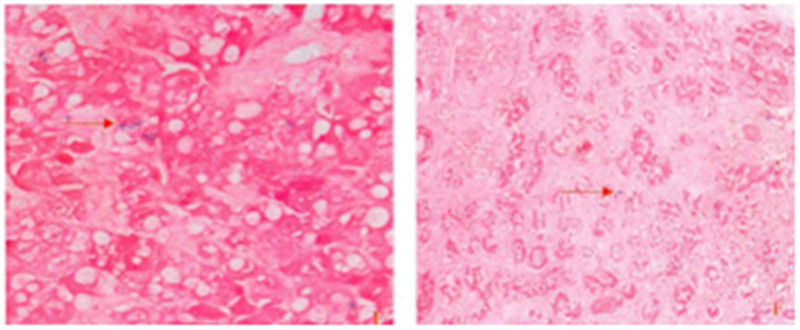

多用于观察病变组织中纤维结缔组织的增生和分布,纤维性肿瘤与肌源性肿瘤的鉴别。对酒精性肝硬化/坏死后性肝硬化及各型肝炎导致的小叶汇管区纤维组织增生程度的差别具有重要价值。Masson染色在肾穿刺活检中可以用于判别在肾小球毛细血管网的系膜氏和上皮下是否存在嗜复红蛋白的沉积,对于肾脏疾病的病理诊断有重要意义。